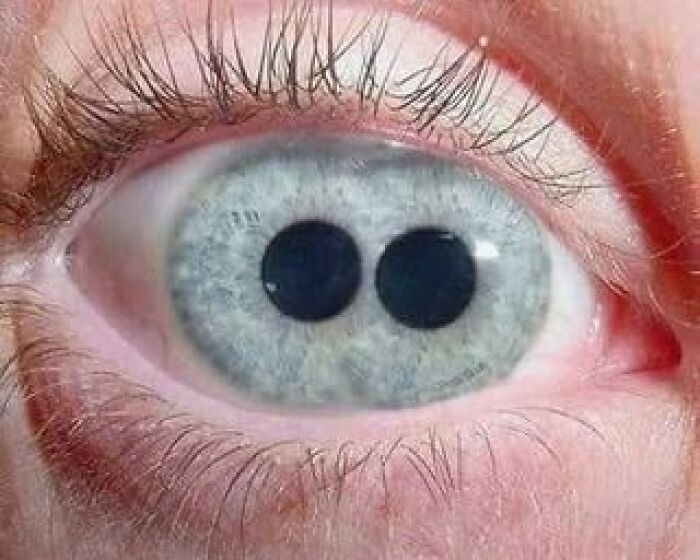

Do People With Polycoria (2 Pupils In One Eye) See Double With That Eye?